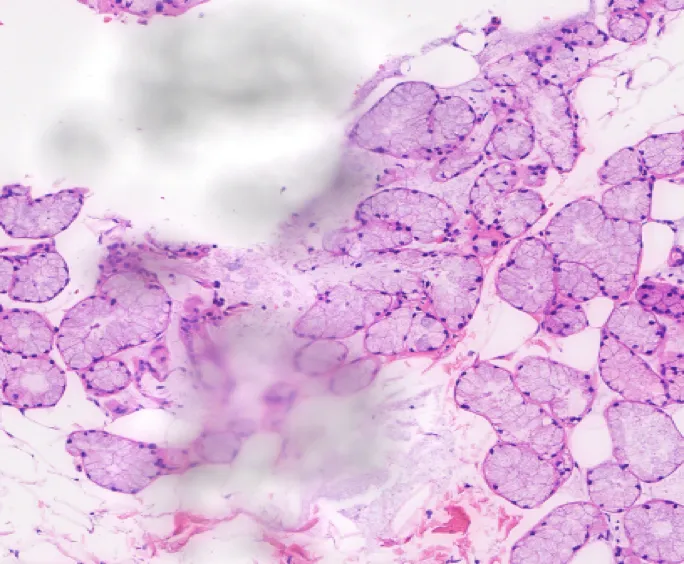

STAINING EFFECT

Equal cell distribution

Clear cytoplasm

Soft and beautiful color

Meet different visual preferences